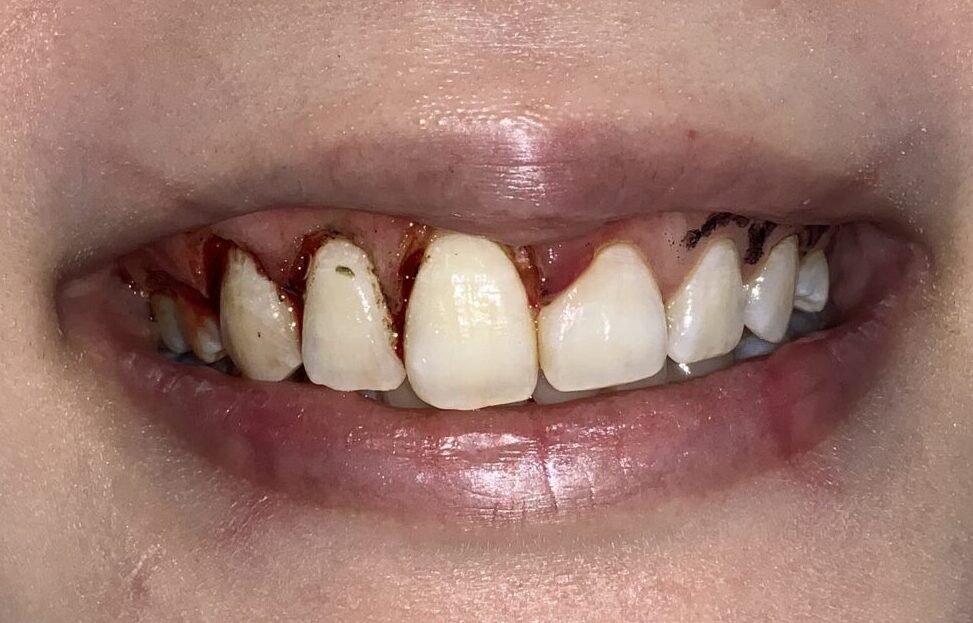

口もとを見てみましょう。

治療の成果がわかるように半分だけの状態で、患者様にもご確認を頂き、大変喜んで頂きました。

歯の形や歯ぐきの形、歯と歯ぐきのマッチング、口もとから見える歯ぐきの状態は完璧です。